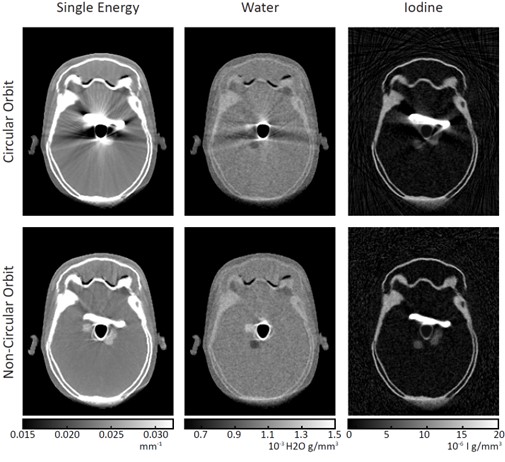

A simulation of head phantoms with metal implants, simulated bleeds, and simulated regions of extravasation was performed and imaged using single energy techniques versus spectral techniques and non-circular orbits versus circular orbits. The combined sinusoidal orbit and spectral technique allowed images with reduced metal artifacts and clear differentiation between the bleed zones and extravasation. Compared with the circular orbit images, there is a clear presence of metal artifacts, and the single energy method (traditional CT) is unable to differentiate between the two materials. The figure above shows the comparison of reconstruction results from circular and non-circular orbits using single energy and spectral measurements.